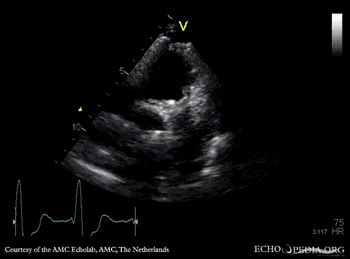

Four prosthetic valves

A4CH: mitral valve prosthesis and tricuspid valve prosthesis A5CH with Color Doppler